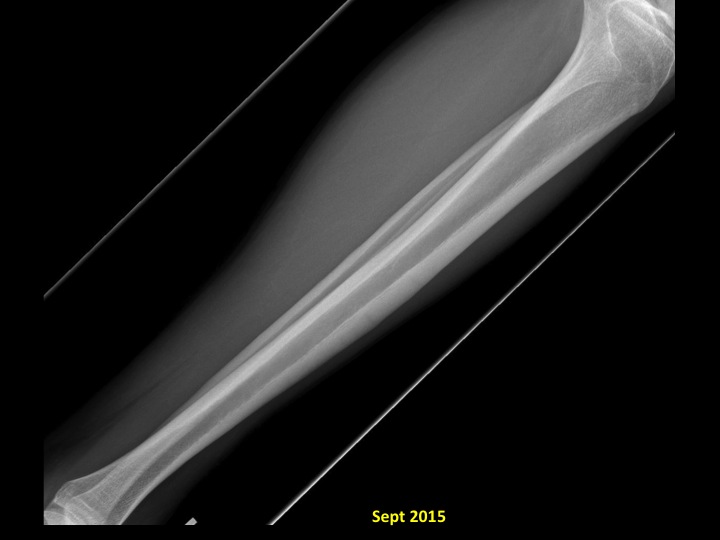

18M with Blau's syndrome and anterior tibial stress fracture

A companion case to #1303, shows a healing anterior tibial stress fracture in a young male with Blaus syndrome, which is an autosomal dominant inflammatory condition with granulomas affecting skin and a symmetrical polyarthritis. We have had a couple of patients presenting with widespread tenosynovitis. I think there may be some overlap with early onset sarcoidosis.

stress fracture ( RID4695 )